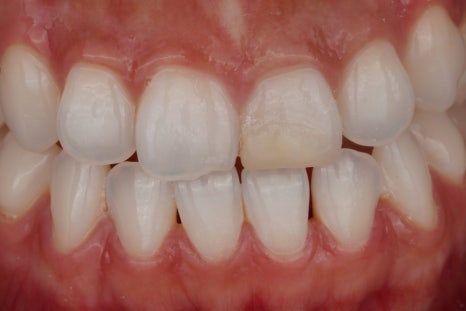

1주 뒤

그리고 변색의 원인이 될 수 있는 신경관 입구 쪽의 약재나 충전물을 정리해 줍니다.

이 과정만으로도 색이 조금 밝아질 때도 있어요.

2주 뒤

그다음에는 치아 내부 공간에 미백 약제를 넣어서 일정 시간 작용하도록 하는데요. 이 약제에서 산소가 발생하며 조금씩 밝게 만들어 주는 원리에요^^

3주 뒤

치아 상태에 따라 한 번으로 끝나는 경우도 있지만 보통은 몇 차례 반복하면서 주변 인접치와 자연스럽게 어울리는 색을 맞춰 가고 있어요.

산소가 빠지려면 충분한 시간을 기다리는 것이 중요하거든요.

완료 후

한 2주 정도 기다리면 이렇게 건강한 자연치와 같은 모습으로 바뀌게 된답니다^^